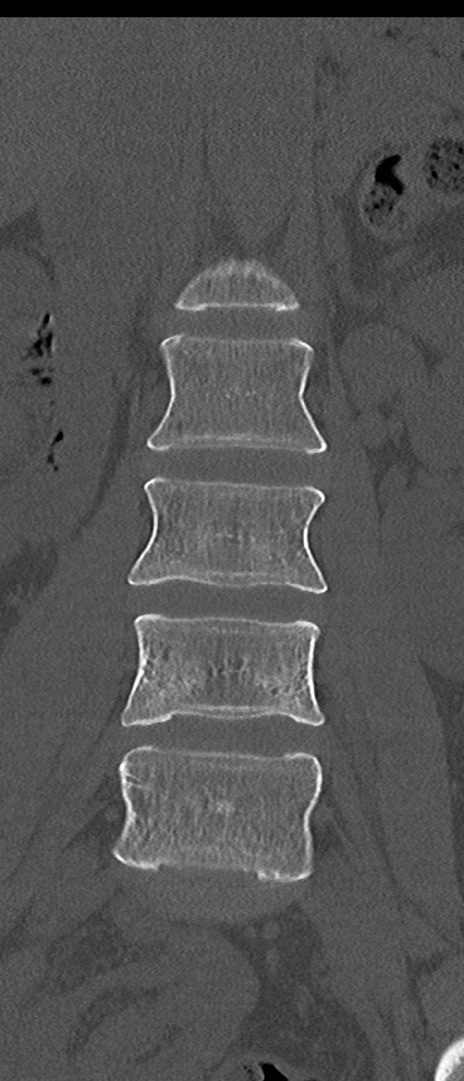

腰椎CT

矢状断像